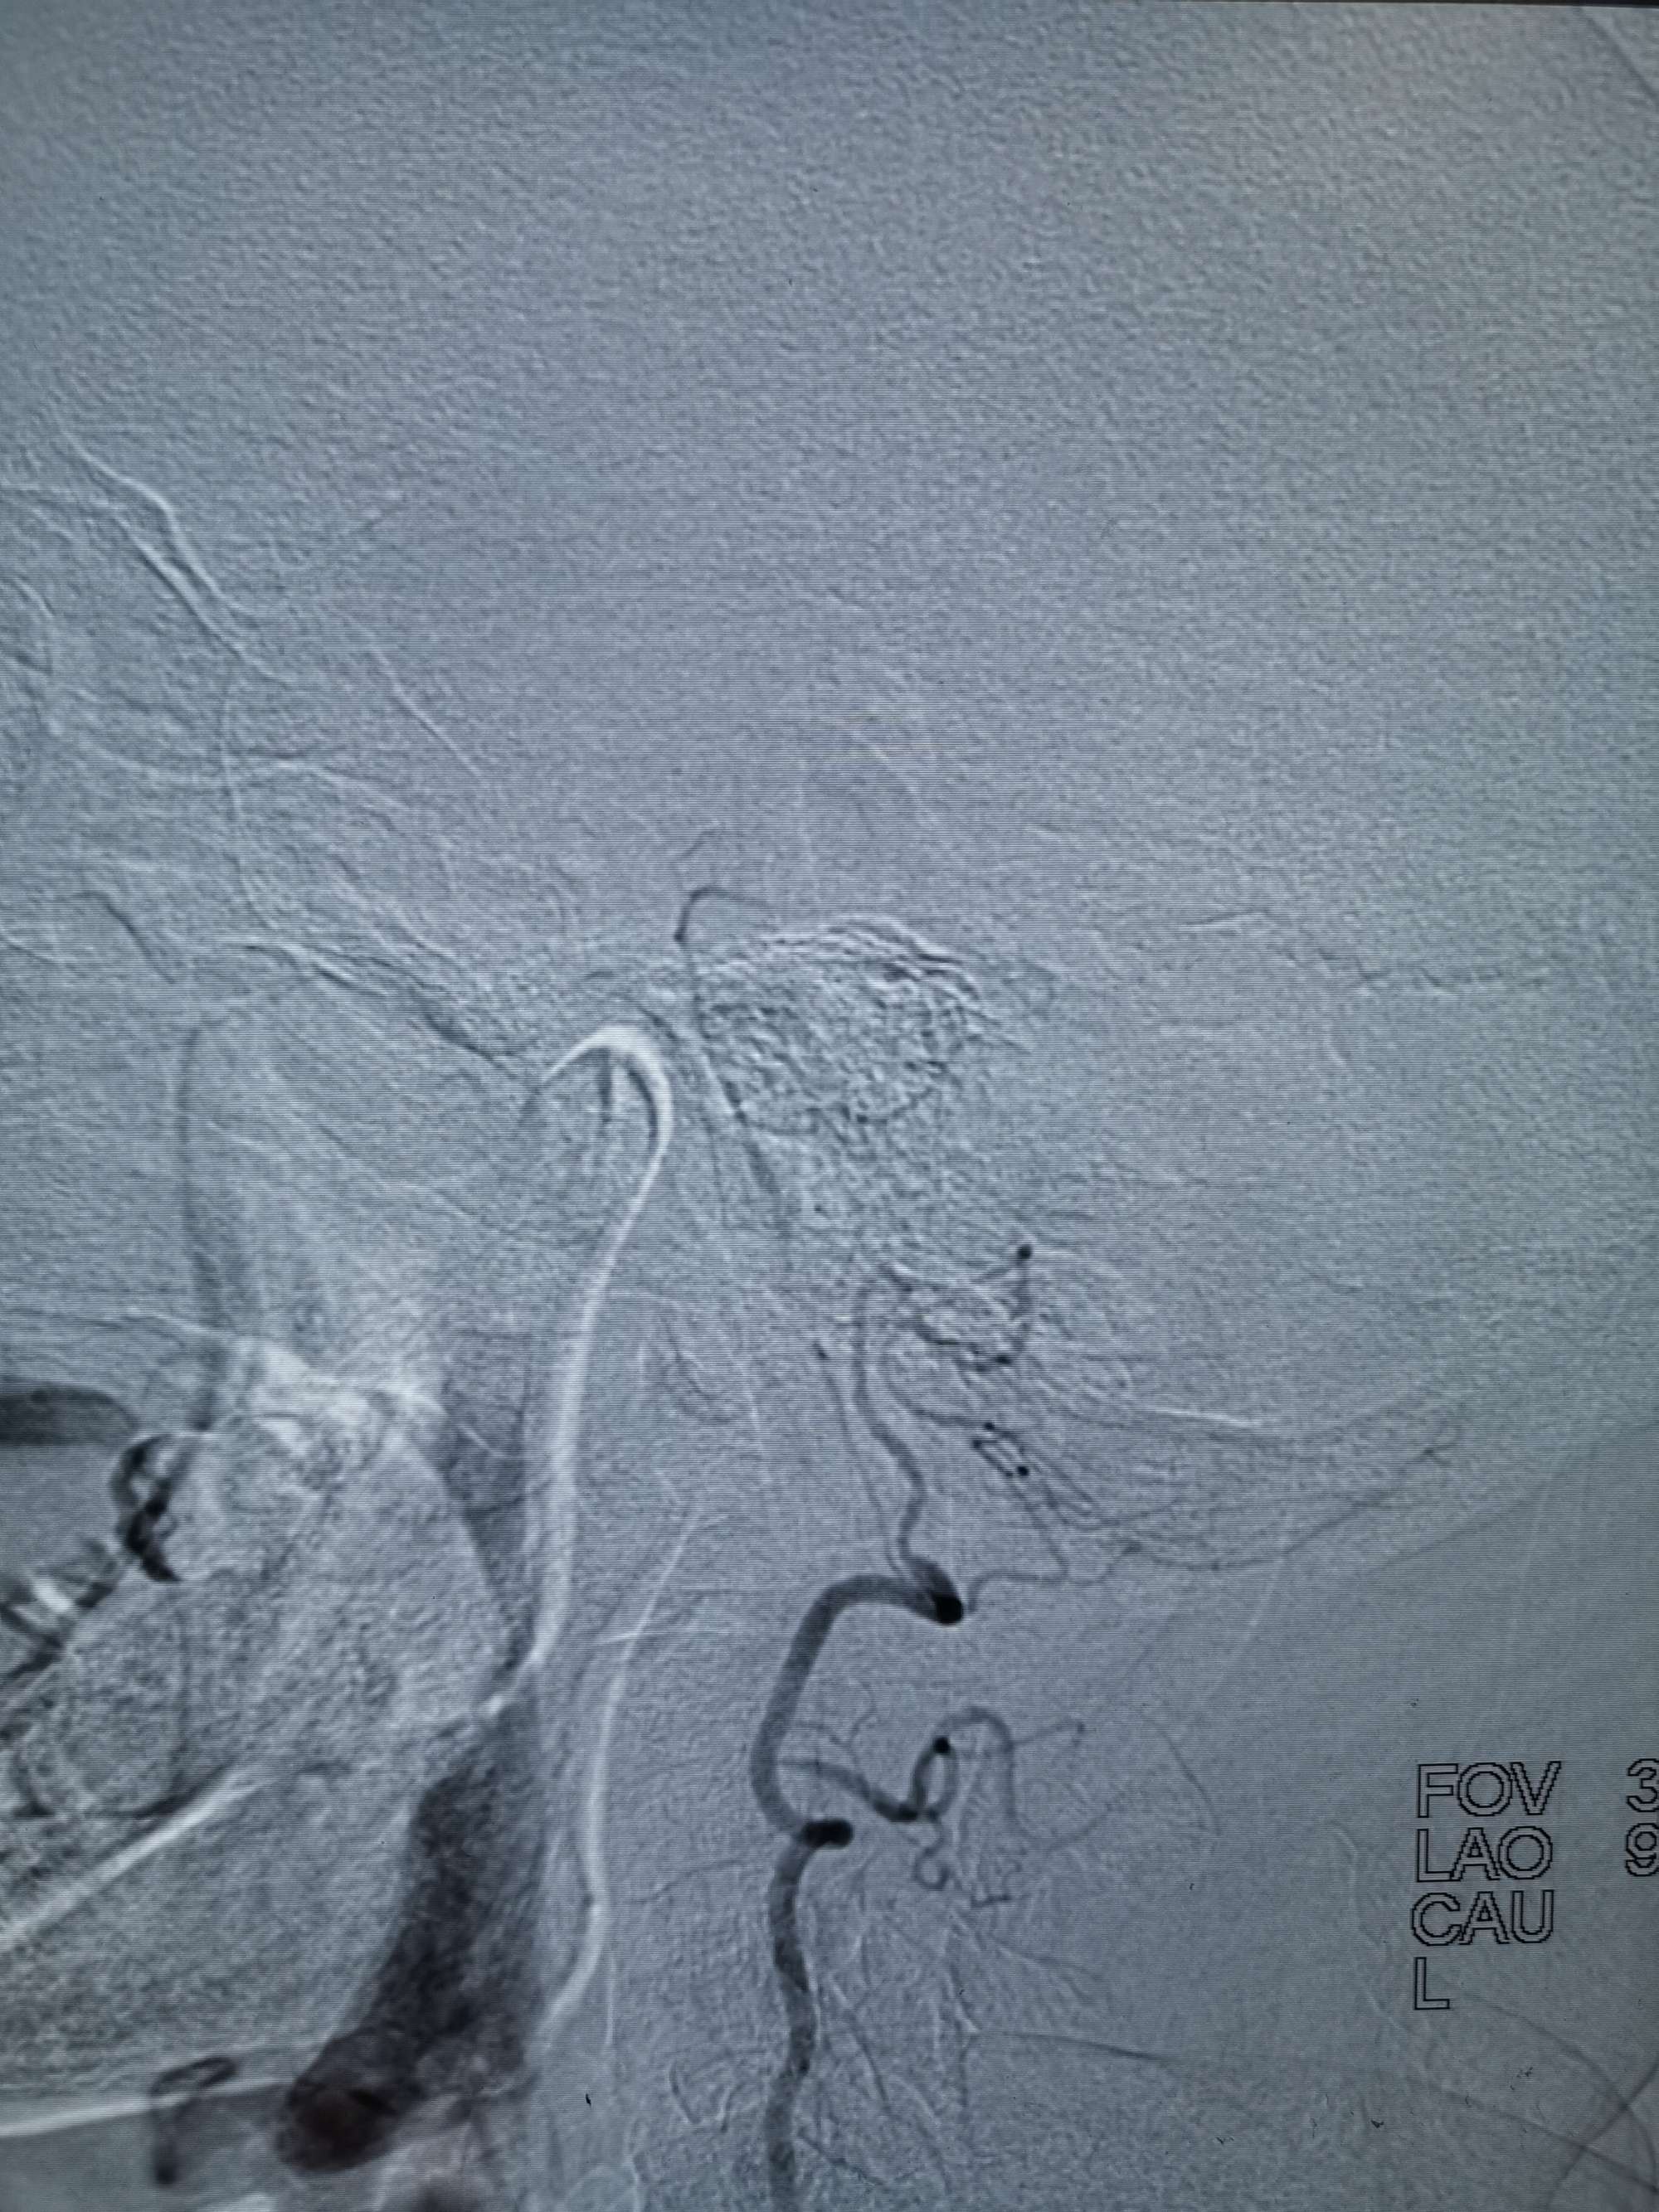

术前再次造影评估

右侧椎动脉穿支供血及左侧PICA供血较入院时略有改善,但改善不明显。故按计划行左侧椎动脉再通术